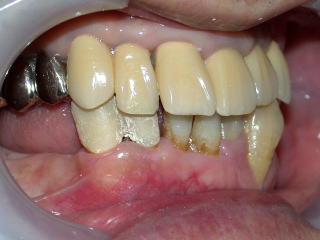

患者さんの希望により全部セラミックスの白い歯を入れることになりました。

インプラント植立費用150.000円とセラミックス5本(87.000円×5本)で

合計585.000円(消費税は不要です)の予定です。